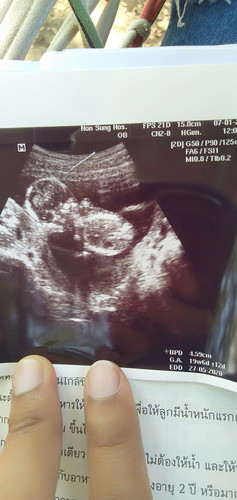

แม่ค่ะช่วสห ดูหน่อยค่ะหญิงหรือชายค่ะ...อยากได้ผู้หญิง

เป็นรูปลำตัวน้องค่ะบอกเพศไม่ได้ แม่ต้องเอารูปหว่างขาน้องมาดูค่ะ

มีภาพหว่างขาไหมคะ ภาพนี้ไม่เห็นเพศค่ะ